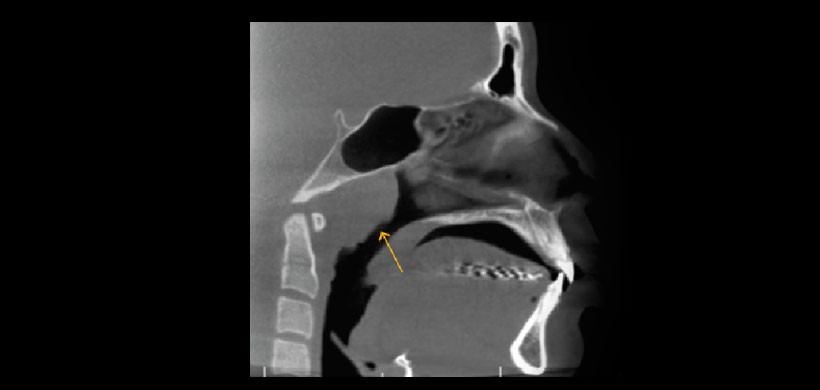

Fig 6. Tomografía volumétrica, vista saital. Muestra fusión de vértebras cervicales (C3 y C4).